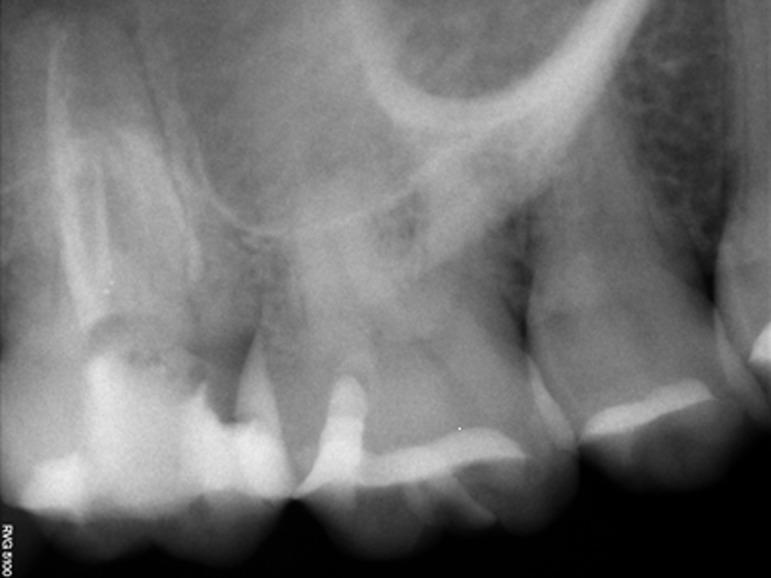

Successful endodontic treatment requires thorough knowledge regarding each root canal system of any tooth and probability of extra canals should be considered. Second maxillary molar with two palatal root canals is not frequent and its incidence reported in literatures is about 0.4-2%. The present case report describes non-surgical retreatment of maxillary second mo-lar with two palatal root canals. Radiographic interpretation is difficult in this region; so, very careful examination of pulpal space and using supportive devices such as loupe and operating microscope is recommended to discover any unusual anat-omic features like extra canals.

成功的牙髓治疗需要对任何牙齿的每个根管系统有全面的了解,并且应考虑存在额外根管的可能性。上颌第二磨牙有两个腭侧根管的情况并不常见,文献报道的发生率约为0.4%-2%。本病例报告描述了对上颌第二磨牙两个腭侧根管进行的非手术再治疗。该区域的影像学解读较为困难;因此,建议非常仔细地检查牙髓腔,并使用放大镜和手术显微镜等辅助设备,以发现任何异常的解剖特征,如额外的根管。